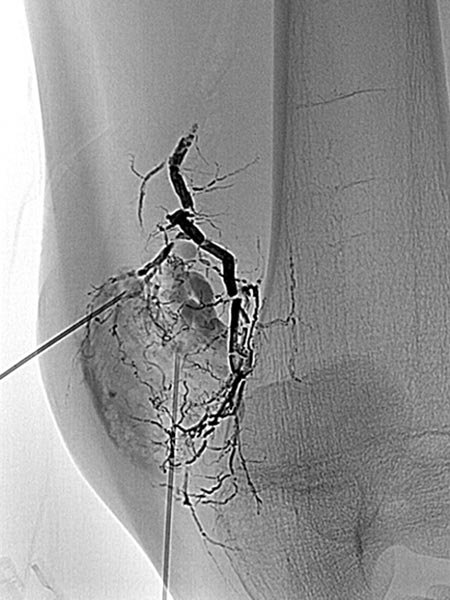

Digital subtraction angiography (DSA) in the early arterial phase shows a dilated feeding artery (so-called “feeder artery”), in this case a medial superior genicular artery. This artery is dilated over time due to chronic hyperperfusion with increased blood flow.

Digital subtraction angiography (DSA) in the arterial phase 2 s later shows some minor arteriovenous fistulas.

Digital subtraction angiography (DSA) in the interstitial and early venous phase again 4 s later shows no direct early venous outflow of the contrast agent but, instead, a pooling phenomenon. In an arteriovenous malformation, an immediate venous outflow would be seen because of multiple direct arteriovenous communications.

Super-selective catheterization of the feeding artery with a microcatheter again depicts multiple, fine arteriovenous fistulas, but not the immediate venous outflow as would be typical of an AVM. However, the visible arteriovenous fistulas are unusually prominent in this venous malformation.

The microcatheter is now used to selectively embolize the fistulas with ethylene-vinyl alcohol copolymer, which as a liquid agent is distributed throughout the fine fistulae.

The radiographic overview after embolization of the AV fistulas shows the selective cast specimen of the radiopaque embolic agent filling the fistulas.

In the final overview digital subtraction angiography after embolization, the fistulas are completely occluded.